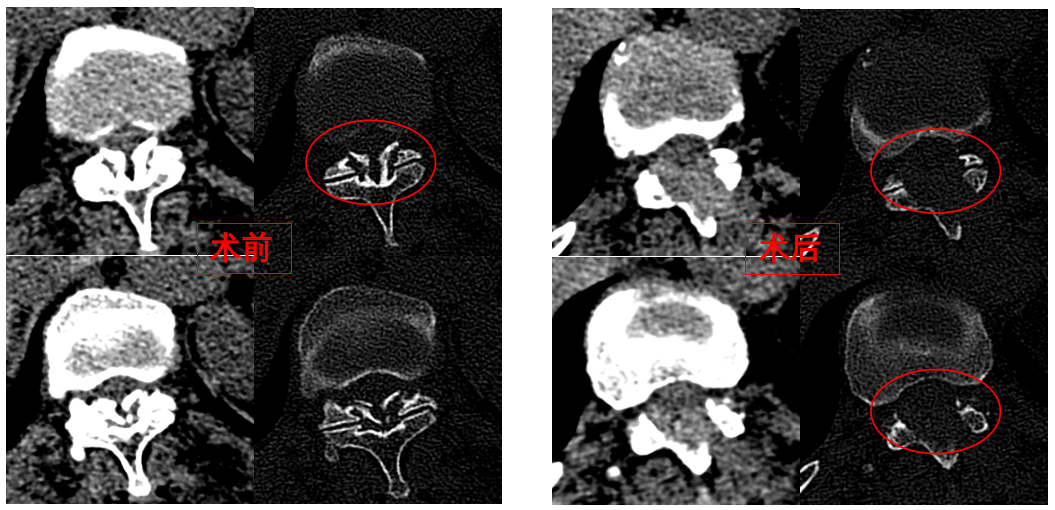

圖為卓瑪阿媽術前、術后胸椎CT照片對比。

華西醫(yī)院成辦分院骨科副主任醫(yī)師張斌接診后,憑借豐富的脊柱治療經(jīng)驗,立即安排卓瑪阿媽做了系列精密檢查,檢查結果顯示,阿媽胸椎11/12節(jié)段黃韌帶嚴重骨化,導致椎管顯著狹窄,脊髓受壓,確診為嚴重的“胸椎黃韌帶骨化癥”,如果不及時手術最終可能面臨癱瘓的風險。

手術歷時一個半小時,骨科脊柱微創(chuàng)團隊成功完整切除了壓迫脊髓的骨化黃韌帶,徹底解除了卓瑪阿媽的脊髓壓迫。手術過程順利,手術切口僅1厘米。